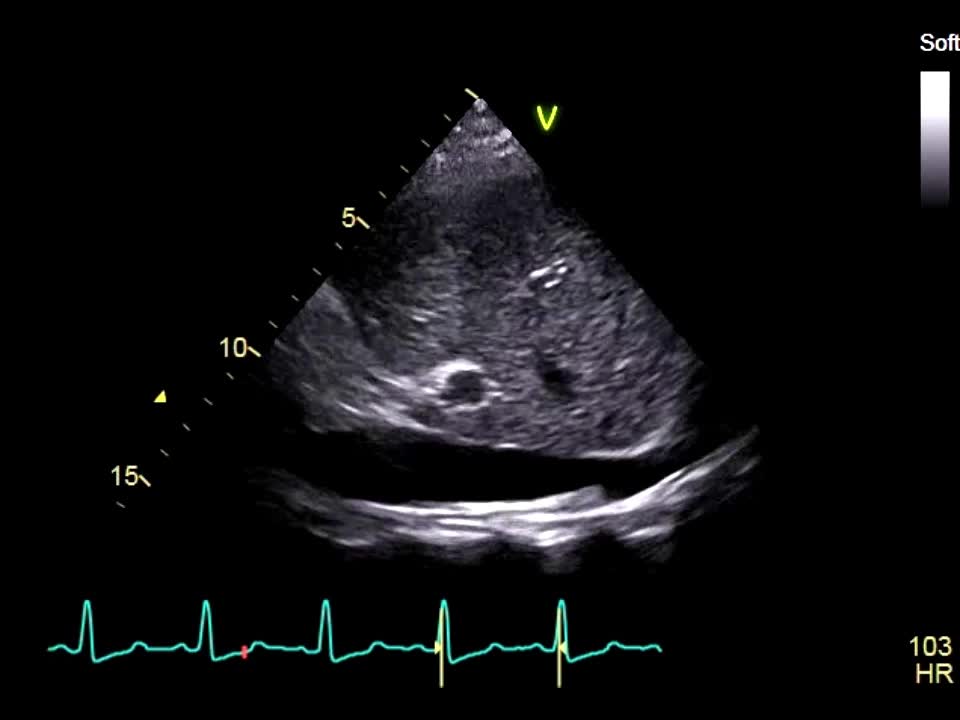

動画19-1 心エコー

00:00:19